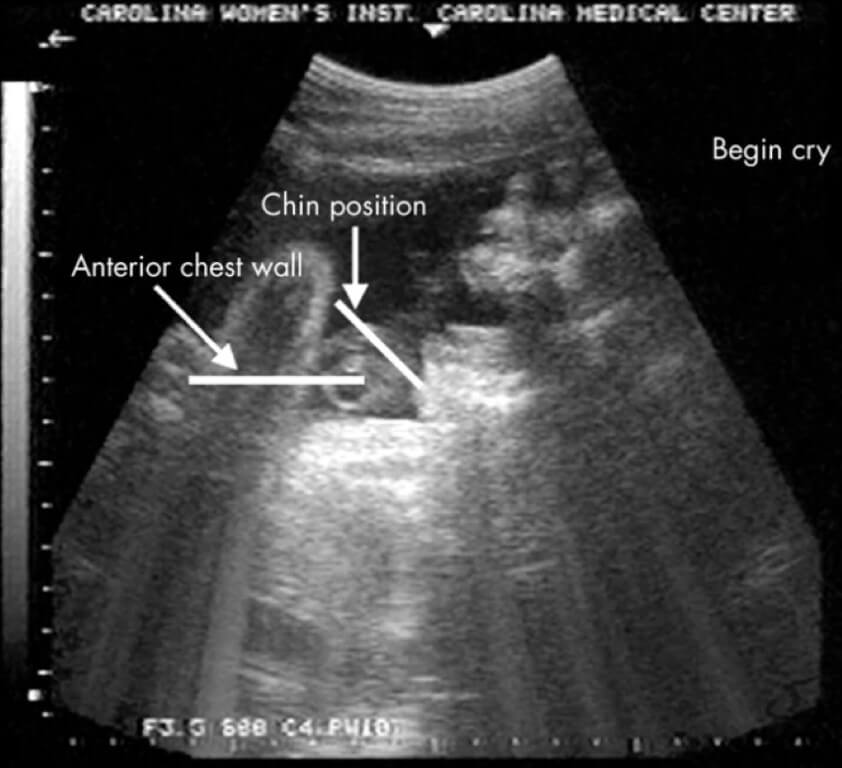

По данным научного издания Science Alert, видео с плачущим в утробе матери ребенком было опубликовано в журнале Archives of Disease in Childhood – Fetal and Neonatal Edition в далеком 2005 году. После стимуляции при помощи вибрации, ученые приложили к животу беременной женщины аппарат УЗИ и заметили, что малыш широко раскрыл рот. При этом он запрокинул голову назад и испустил три глубоких выдоха. Вдобавок к этому, врачи заметили дрожание подбородка — это явный признак плача. Такая реакция на стимуляцию была замечена у 10 плодов, что является 6% от общего числа изученных младенцев.

Расположение передней грудной стенки и подбородка во время плача